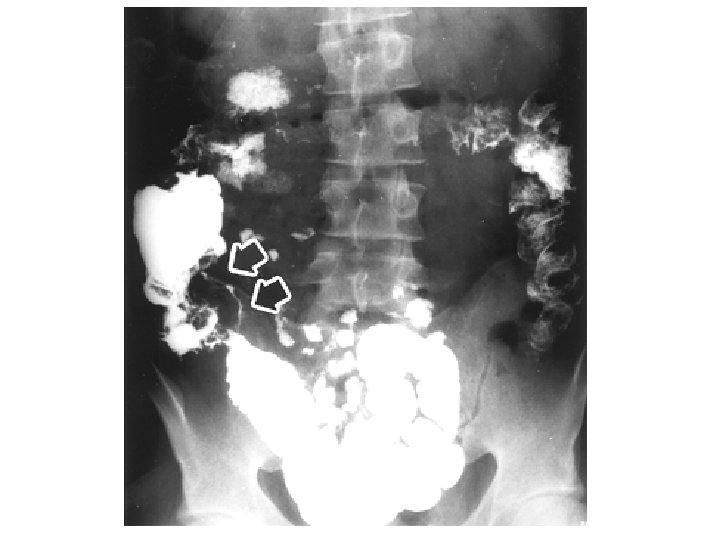

Clisma opaco Anatomia patologica Cancro del colon 77